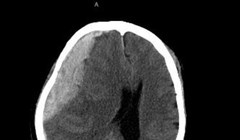

VietTimes – Dị dạng mạch máu não là căn bệnh nguy hiểm, có thể dẫn đến vỡ mạch, gây đột quỵ, động kinh co giật. Để giúp người dân phòng tránh bệnh này, ngày 31/10, Bệnh viện Hữu nghị Việt Đức sẽ tổ chức khám và tư vấn miễn phí với sự tham gia của PGS.TS. Đồng Văn Hệ - Phó Giám đốc Bệnh viện Hữu nghị Việt Đức, Chủ tịch Hội Phẫu thuật Thần kinh ASEAN.

VietTimes – Hàng trăm người có dấu hiệu bị bệnh tim mạch

đã được các bác sĩ của Bệnh viện Việt Đức khám và tư vấn miễn phí trong ngày 21/12,

nhờ đó, đã phát hiện để điều trị bệnh biến mạch máu não cho nhiều người.